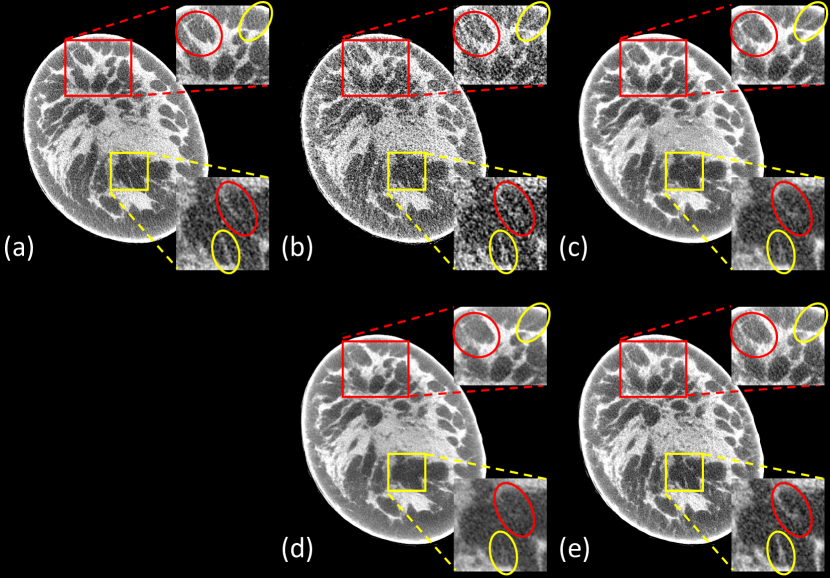

Figure 2: Representative slices reconstructed using different methods for Koning dataset. (a) Ground-truth, (b) FDK from 75-view cone-beam data, (c) Residual-CNN, (d) FBPConvNet, (e) DEER. The red boxes mark the Regions of Interest (ROIs). Yellow circles mark some subtle details in the ROIs. The display window is [-200, 200] HU for visualizing breast details. Note that the final reconstructions were post-processed to remove irrelevant structures outside the field of view.

Refer to caption

Figure 3: Representative slices reconstructed using different methods for Koning dataset. (a) Ground-truth, (b) FDK from 75-view cone-beam data, (c) Residual-CNN, (d) FBPConvNet, (e) DEER. The red and yellow boxes mark the Regions of Interest (ROIs). Red and yellow circles mark some subtle details in the ROIs. The display window is [-200, 200] HU. Note that the final reconstructions were post-processed to remove irrelevant structures outside the field of view.

To visualize the performance of different methods, a few representative slices were selected from the testing dataset. Figs. 2 and 3 show results reconstructed using different methods from 75-view cone-beam projections. For better evaluation of the image quality, the regions of interest (ROIs) marked in the red/yellow boxes in both figures are magnified. Three metrics, including Peak Signal to Noise Ratio (PSNR) [46], SSIM [42], and MAE [41], were computed for quantitative assessment. The quantitative results are shown in Table I.

Our proposed DEER network produced few-view denoising results comparable or superior to that from both image-domain methods. All of the deep-learning methods could effectively remove streak artifacts introduced by the few-view constraint. Particularly, the DEER network produces better reconstructions in the selected ROIs. Both image-domain methods tend to smooth out some subtle details embedded in the noisy background due to insufficient data. For example, in Fig. 2, the breast feature inside the yellow circle is hardly distinguishable in Fig. 2 (c) and (d). Also, in Fig. 3, the feature in the red circle of red ROI and the features in the yellow ROI are hardly visible in the image reconstructed by FBPConvNet.

For the Residual-CNN method, the intensity of certain features is dimmer than expected in the reconstructed breast slices (feature in the yellow circle of Fig. 2, and features in the yellow ROI of Fig. 3). Moreover, the FBP method is associated with artifacts that do not exist in the ground-truth images, and in some cases, the image-domain methods cannot remove these artifacts through convolutional operations. For example, the artifact in the yellow circle of red ROI in Fig. 3 is clearly visible in the image produced by Residual-CNN, but this artifact is mostly removed by DEER through a learnable network-based reconstruction algorithm.

For the quantitative assessments, DEER had better SSIM and MAE values and a slightly lower PSNR value than FBPConvNet. FBPConvNet achieved the best PSNR value due to the implementation of the Mean Squared Error (MSE) based objective function. However, the literature has discussed that higher PSNR values do not guarantee the denoising performance, especially the textural/visual similarities relative to the ground-truth images [47, 5]. Also, it should be noted that since both FBPConvNet and residual-CNN only use a single loss function for optimization, these two methods may be subject to potential losses in visual performance. Both loss functions have their own limitations, and one should not solely rely on them for estimating image quality [48, 49]. Even though DEER does not achieve significant improvements quantitatively, images reconstructed by DEER present promising visual comparisons. Moreover, as presented in Figs. 2 and 3, the images reconstructed by FBPConvNet appear over-smoothed with less visual image texture, which is not desirable in clinical diagnosis. Lastly, the implementation of WGAN framework may negatively affect the quantitative measurements but it provides better recovery of subtle details and structural features [5, 50]. Compared with the other deep learning methods, DEER demonstrates a competitive performance in removing artifacts and reserving subtle but vital details compared with the other methods. In terms of reconstruction time, DEER takes about 0.1422 seconds to reconstruct a single 2D slice (1024×1024102410241024\times 1024) on an NVIDIA Titan RTX GPU.